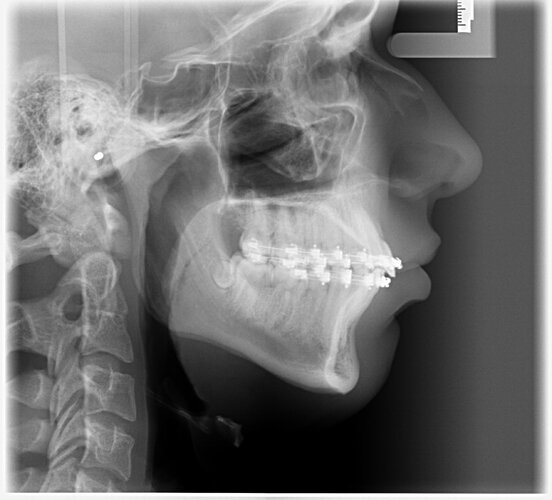

I got bimax surgery + genioplasty 4 days ago at age 17.

I'm scared that my chin will be underadvanced once the bloat is gone. Idon't feel much bloat on my chin and i'm very happy with the sideprofile so i hope the chin won't be retrognathic once the bloat is gone.

What do yall think abt the result 4 days post op, do you think it's a good bimax and which changes can yall see?

I'm scared that my chin will be underadvanced once the bloat is gone. Idon't feel much bloat on my chin and i'm very happy with the sideprofile so i hope the chin won't be retrognathic once the bloat is gone.

What do yall think abt the result 4 days post op, do you think it's a good bimax and which changes can yall see?